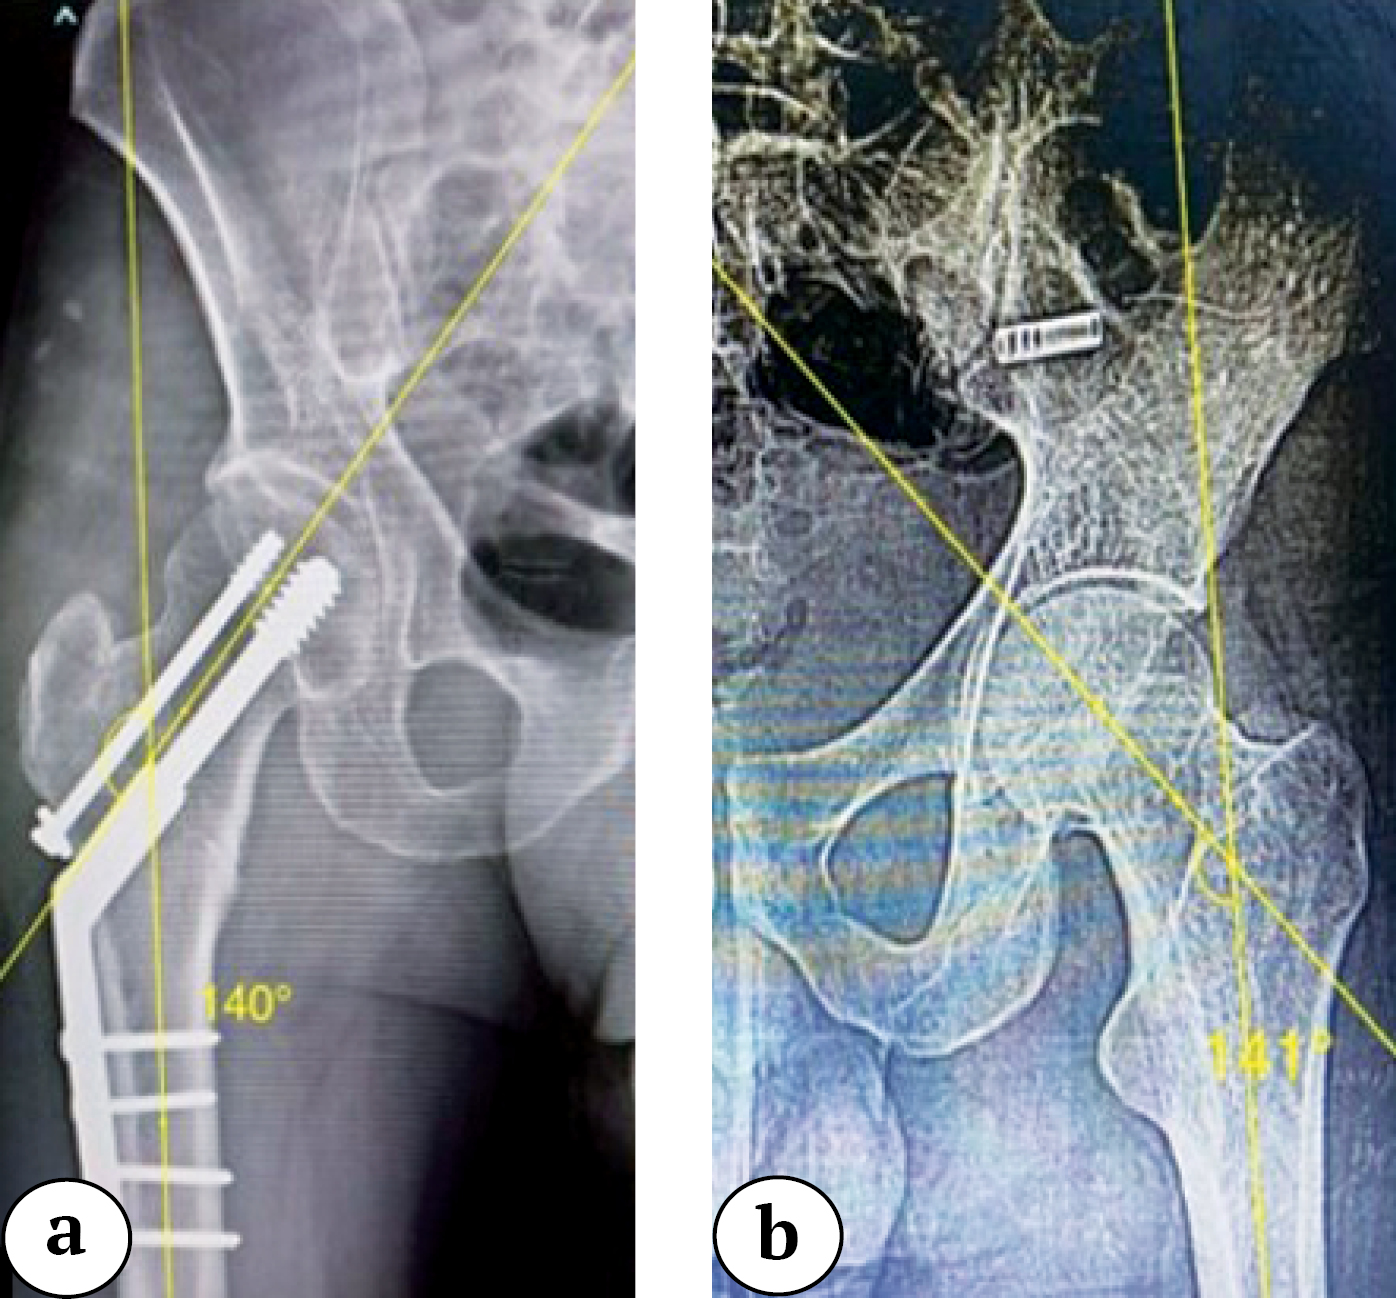

No significant difference in neck shaft angles was observed postoperatively compared to the contralateral side in either PFN or DHS groups (Table 4, Figures 3, 4).

Figure 3. X-ray of a patient from the DHS group: a — postoperative neck-shaft angle; b — neck-shaft angle of contralateral unaffected side

Figure 4. X-ray of a patient from the PFN group, showing 5 degrees of varus malalignment as compared to the unaffected contralateral side